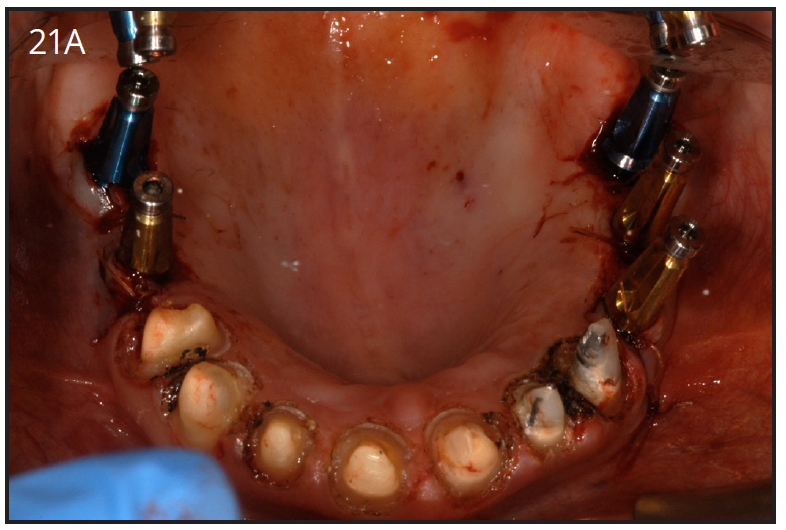

After 4 to 6 months of healing post-implant surgery, the final restoration is fabricated. An impression is taken either at implant level or at the abutment level to fabricate the final crown. The implant level impression records the implant position, so it needs to be very precise. An impression coping is screwed onto the implant to be transferred into the impression. The copings are utilized for a closed-tray technique or open tray technique. The closed tray technique may be used mostly with one implant, but the open-tray technique is used for multiple implants, when different implant angles exist. (Figures 21A, 21B) With either technique, the impression material most often recommended is polyether.34 Bite registration, shade selection, and opposing models are collected in the usual manner, as for crown and bridge cases.

Figure 21A – Closed tray impression copings

Figure 21A